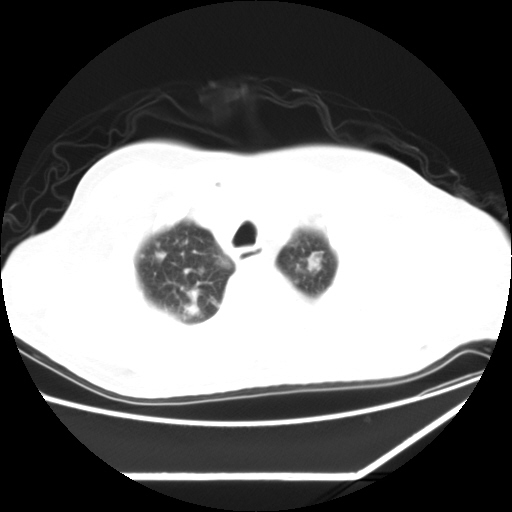

男,57,畏寒,发热

双肺多发结节样病灶,部分内见透光区,纵隔内见淋巴结肿大。结核临床如有畏寒,高热,白细胞增高首先考虑迁徙性肺脓肿(多是金黄色葡萄球菌感染)。

注意除外转移瘤。

双肺典型的亚急性粟粒性肺结核

双侧胸膜结核